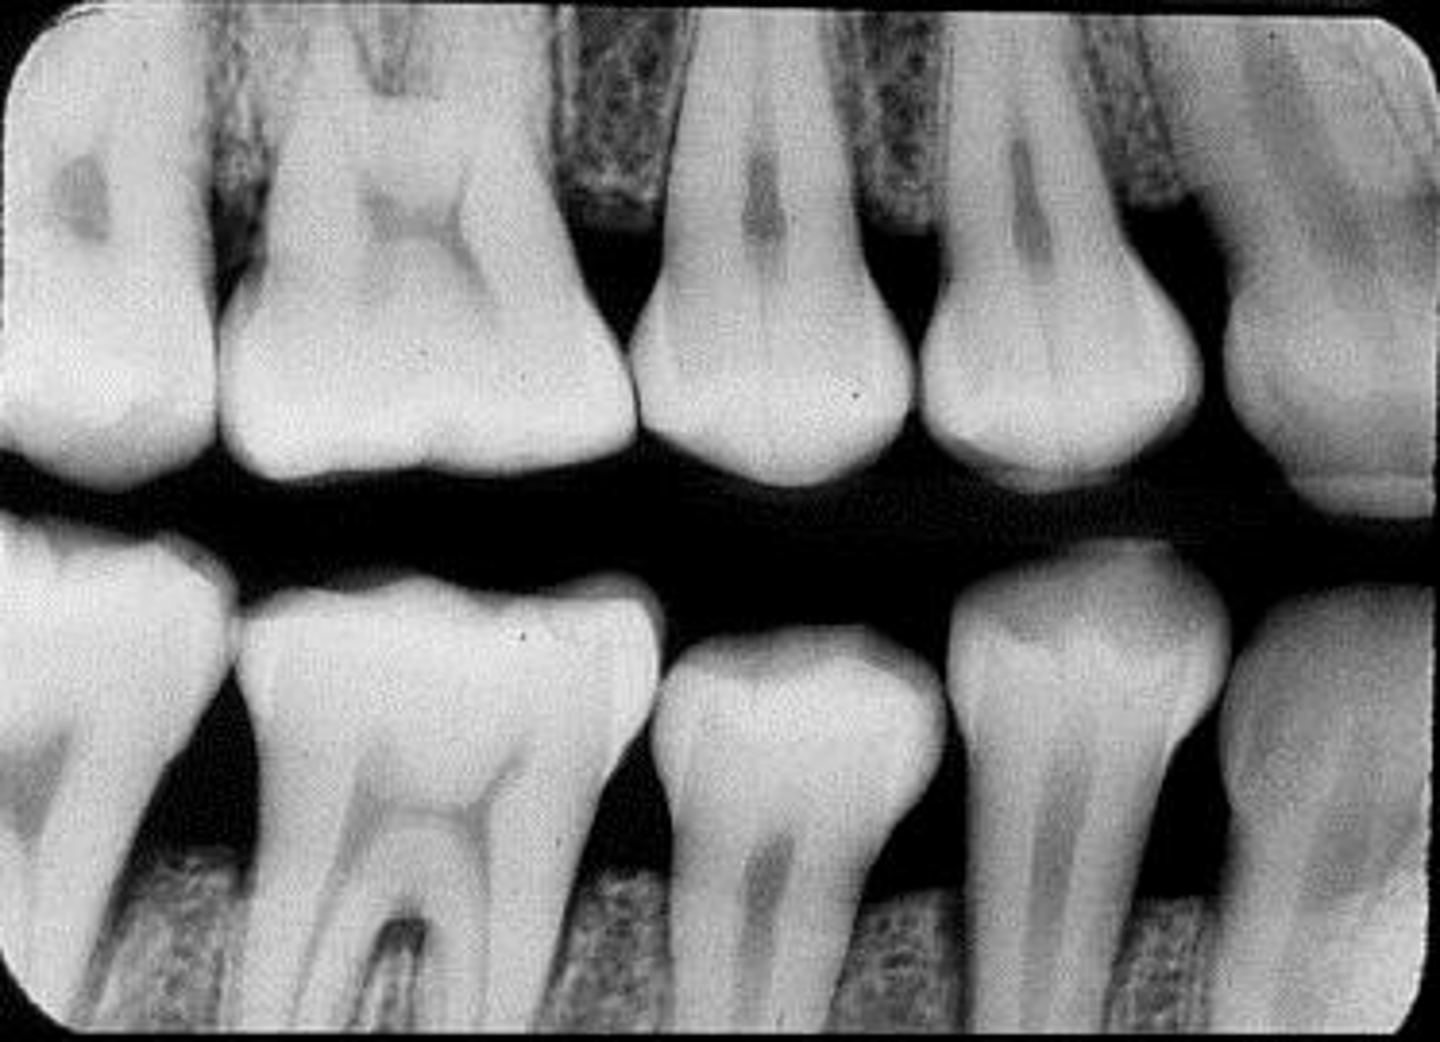

What is this projection of?

Premolars projection